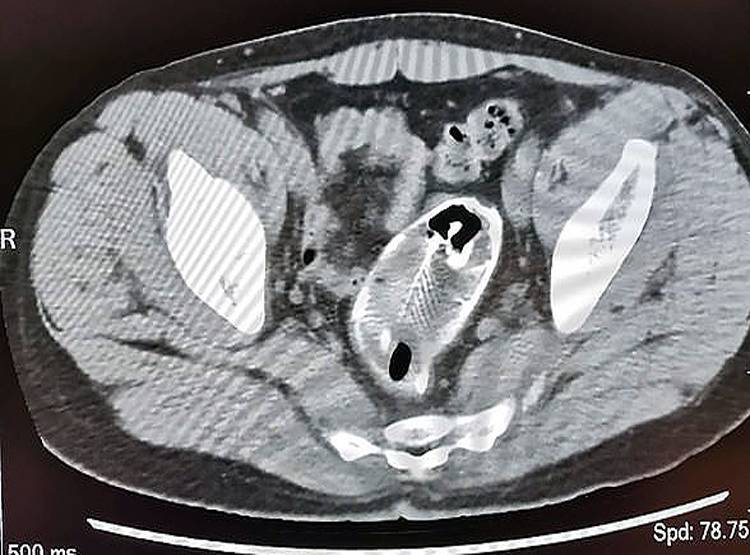

हुआ यूं कि चीन के गुआंगडोंग प्रांत के झाओक्विंग में एक 30 वर्षीय युवक ने बताया कि वह गलती से एक मछली के ऊपर बैठ गया. ये मछली उसे मलाशय (Rectum) से होते हुए पेट तक पहुंच गई. इस दौरान मछली ने बड़ी आंत में काफी घाव कर दिया. बड़ी आंत में फंसी मछली का एक्स-रे.

जब उस युवक को पेट में दर्द होने लगा और वह खुद से मछली नहीं निकाल पाया तो वह झाओक्विंग फर्स्ट पीपुल्स अस्पताल पहुंचा. उसने डॉक्टरों को ये बात बताई कि वह गलती से मछली के ऊपर बैठ गया था. मछली गुदा द्वार से शरीर के अंदर पहुंच गई. बड़ी आंत में फंसी मछली का एक्स-रे.

डेलीमेल वेबसाइट की खबर के अनुसार डॉक्टरों ने तत्काल एक्स-रे निकाला. उसमें मछली बड़ी आंत में फंसी हुई दिखाई दे रही थी. इसके बाद डॉक्टरों ने पहले तो युवक के मलाशय से मछली निकालने की कोशिश की लेकिन मछली काफी बड़ी थी, इसलिए पेट का ऑपरेशन किया गया.